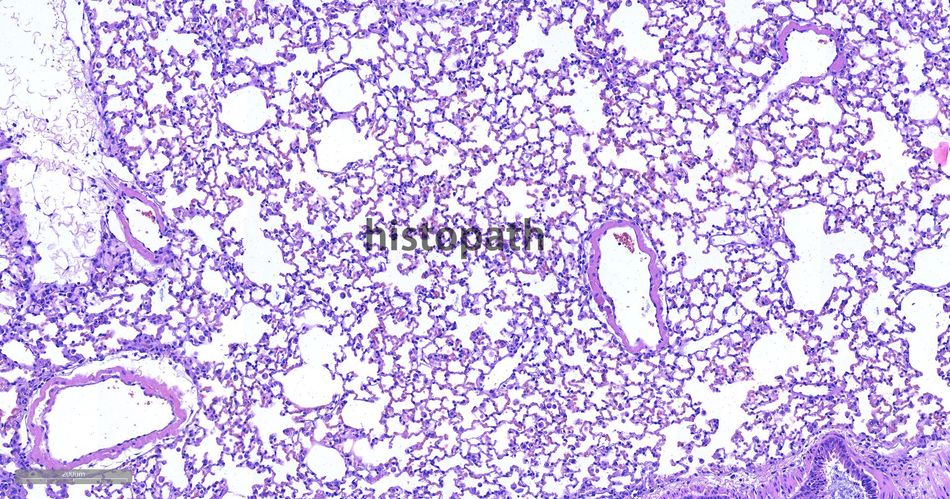

苏木精--伊红染色法(hematoxylin-eosin staining),简称HE染色法,石蜡切片技术里常用的染色法之一。苏木精染液为碱性,主要使细胞核内的染色质与胞质内的核酸着紫蓝色;伊红为酸性染料,主要使细胞质和细胞外基质中的成分着红色。HE染色法使组织学、胚胎学、病理学教学与科研中最基本、使用最广泛的技术方法。

染色结果:

细胞核呈蓝色,细胞质、肌肉、结缔组织、红细胞、嗜曙红颗粒呈不同程度的粉红色。钙盐、软骨基质和各种微生物也可染成蓝色或紫蓝色。核仁呈红色。着色情况不仅与组织或细胞的种类有关,也随其生活周期及病理变化而改变。质量优良的HE染色切片样本,细胞核与细胞质蓝红对比明显,胞核鲜明,核膜及核染色质颗粒均清晰可见。